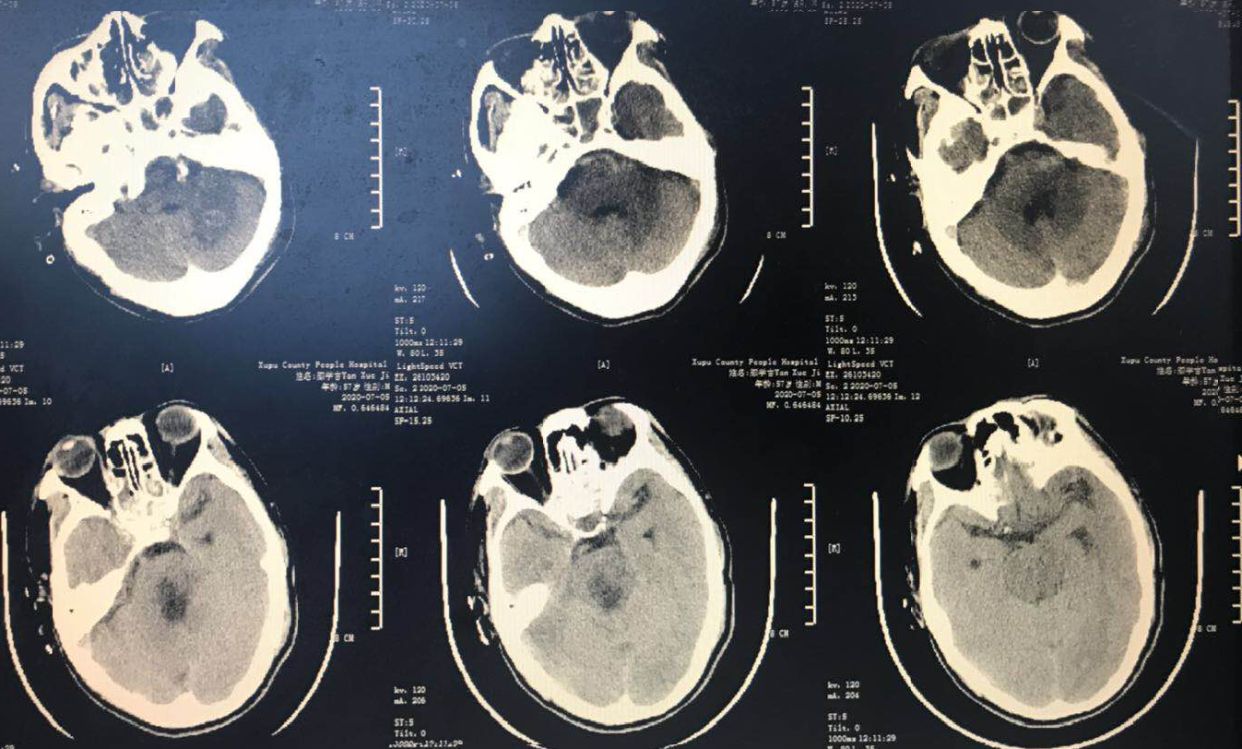

复查置管位置满意

7月5日复查